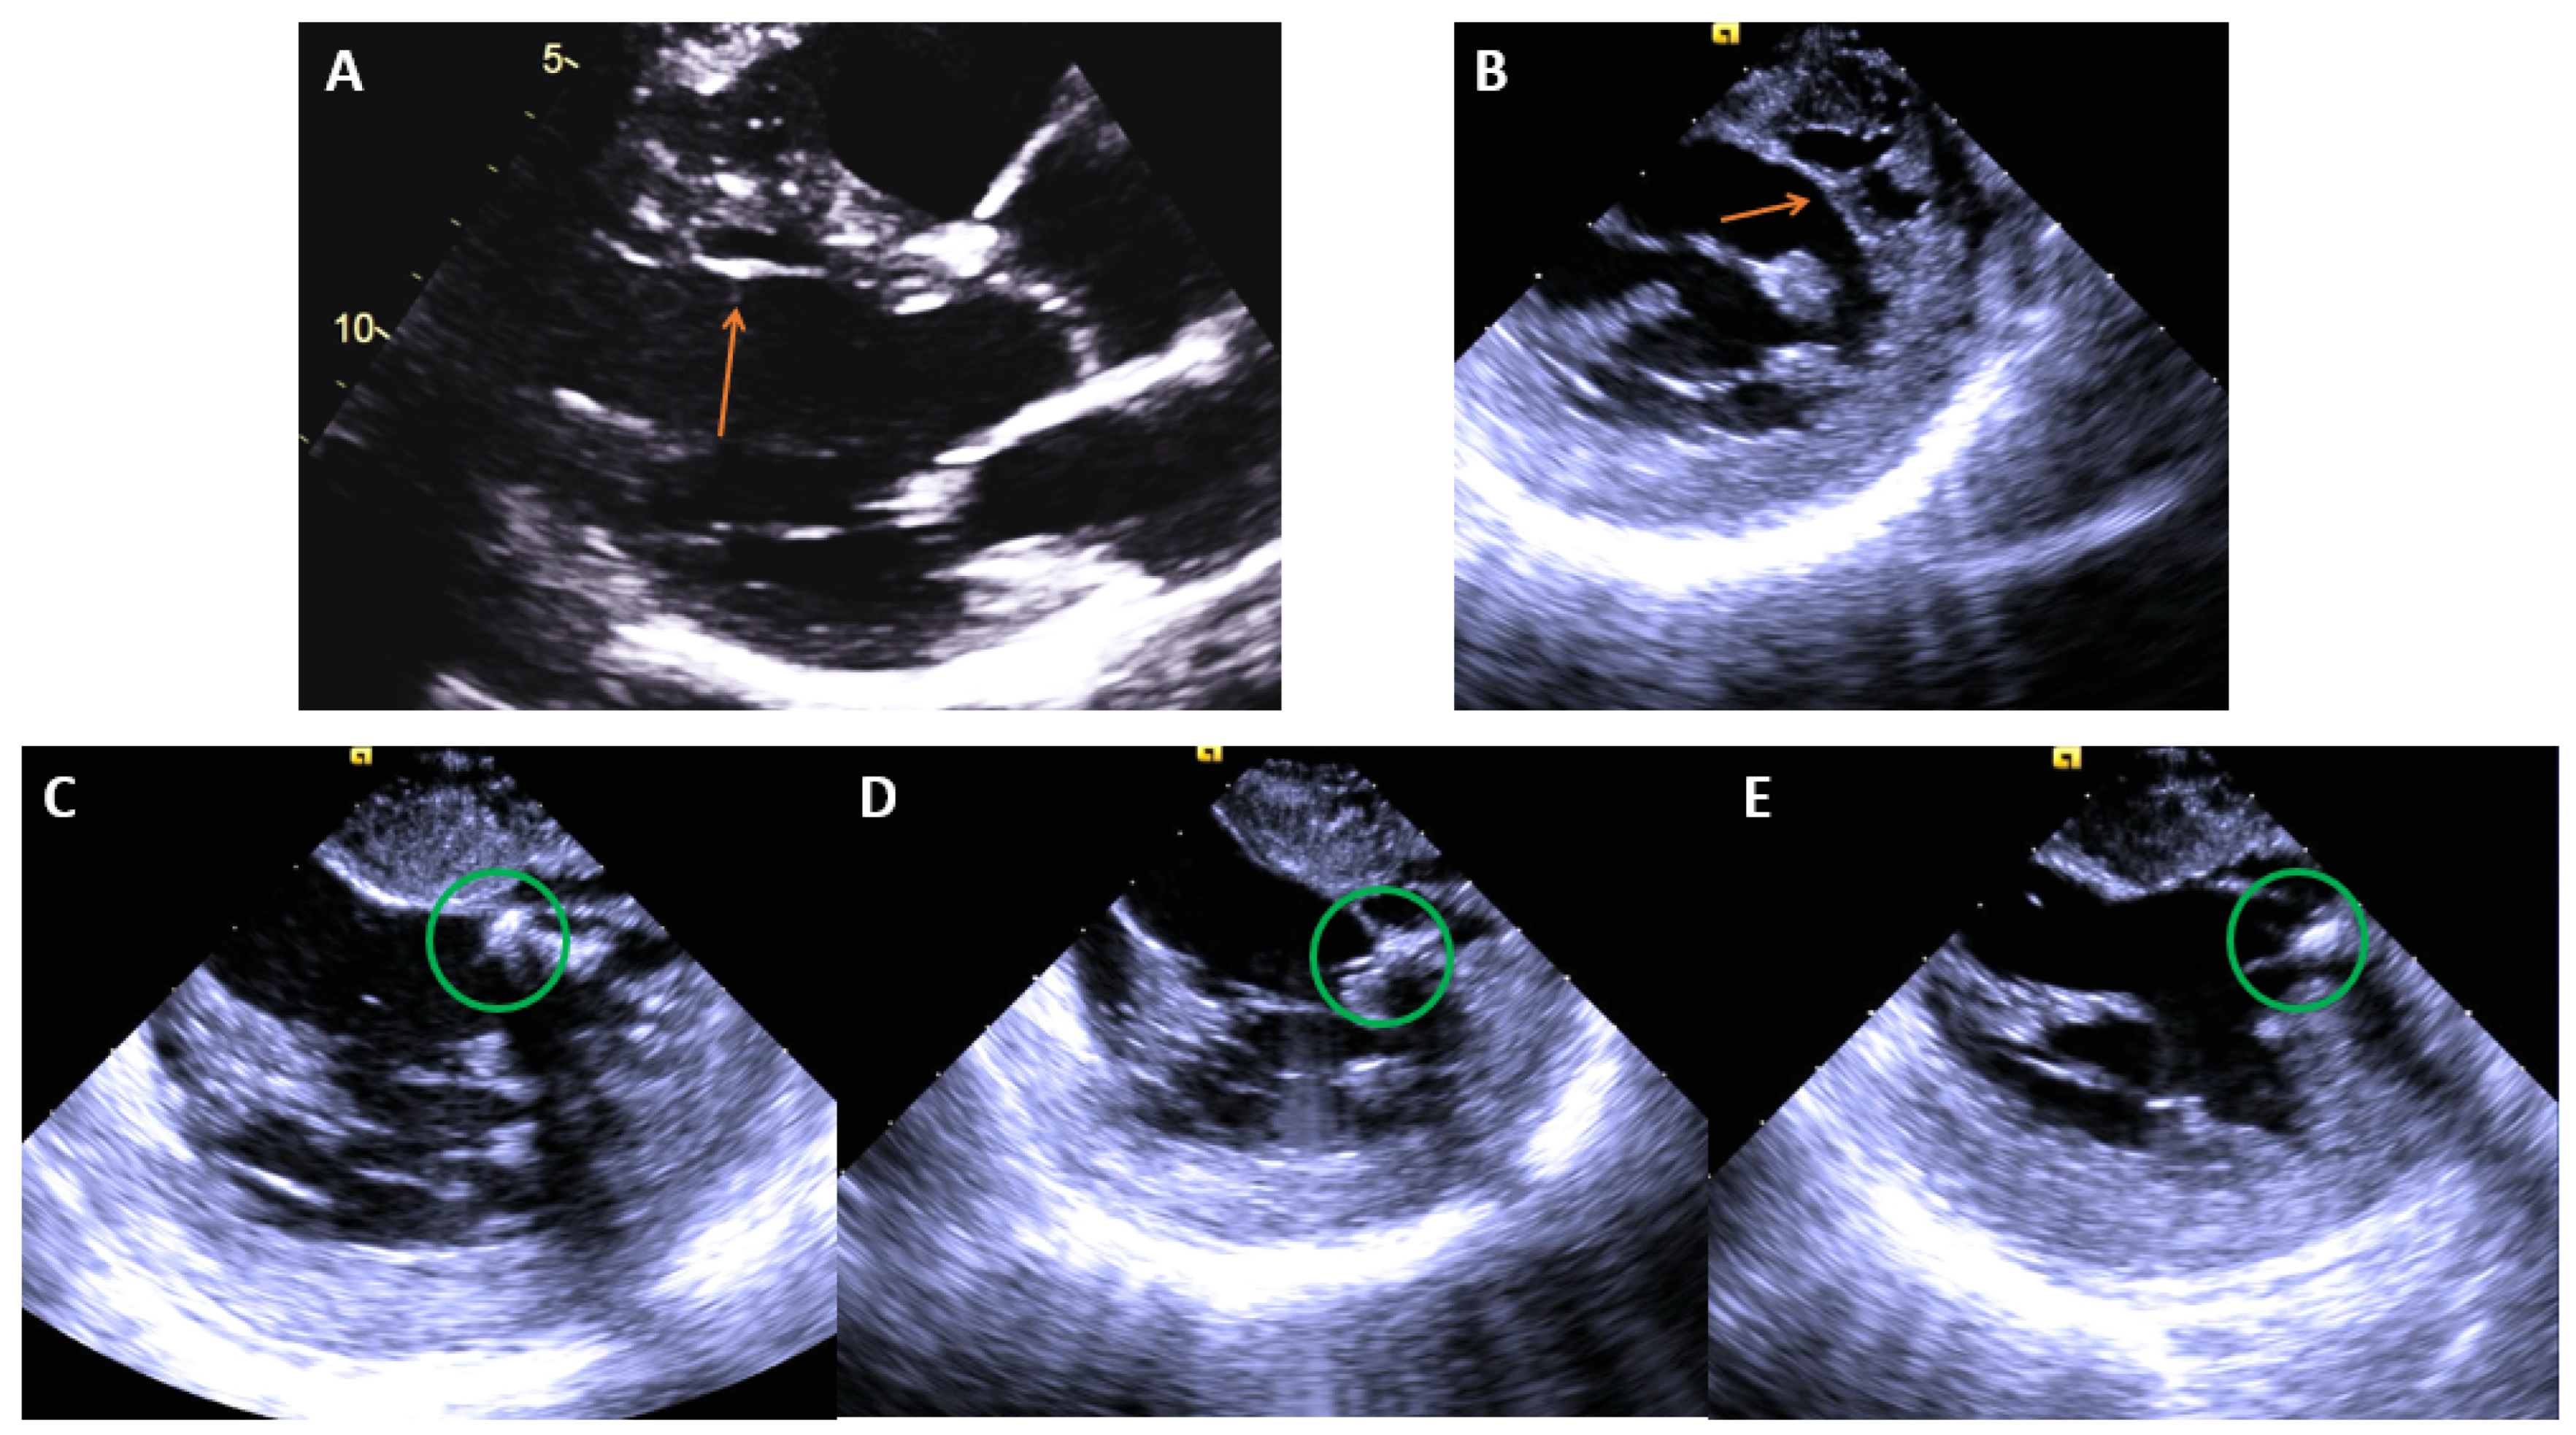

| Papillary Muscle VT Ablation Tips |

|---|

|